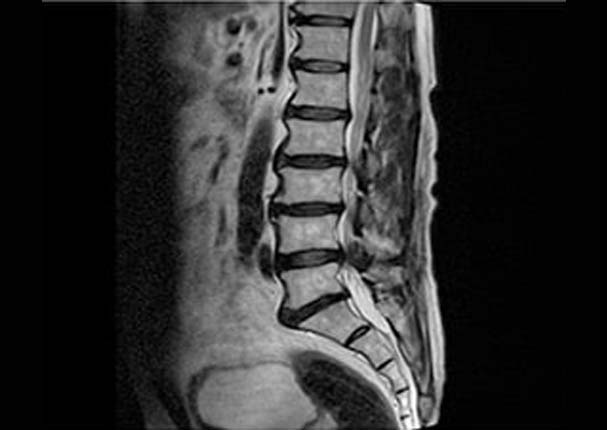

노화 및 여러 요인으로 인해 황색인대가 비대해져 신경을 누르고 있는 모습

고화질 신형 MRI와 디지털 X-RAY 장비를 사용해 병변 부위를 정확하고 정밀하게 검진합니다.